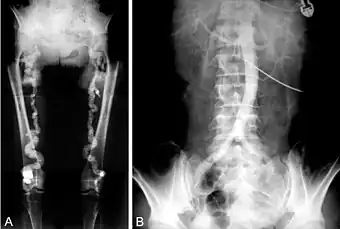

A. Pelvic and lower extremity radiograph shows extensive calcification of the femoral arteries. B. Translumbar aortography shows near-total obstruction of the femoral arteries.